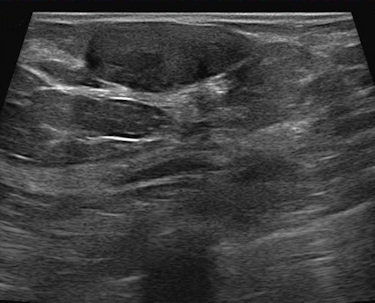

At the same time, dense tissue makes abnormalities more difficult to read, especially on traditional film-screen mammography. The landmark Digital Mammographic Imaging Screening Trial (DMIST) demonstrated better detection of dense-breast abnormalities using full-field digital mammography (area under the curve [AUC] 0.78 ± 0.02) versus film-screen mammography (AUC 0.68 ± 0.03).

"Dense breasts can mask cancer that's there, reducing contrast," Astley said. "Its effect on CAD isn't clear-cut; there is conflicting evidence in the literature. Some say it tends to reduce the performance of CAD, while other work shows no effect."